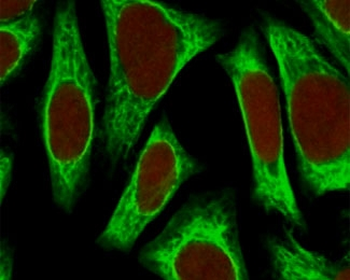

Immunofluorescent staining of fixed human HeLa cells with Smooth Muscle Actin antibody (clone SPM332, green) and NucSpot nuclear stain (red).